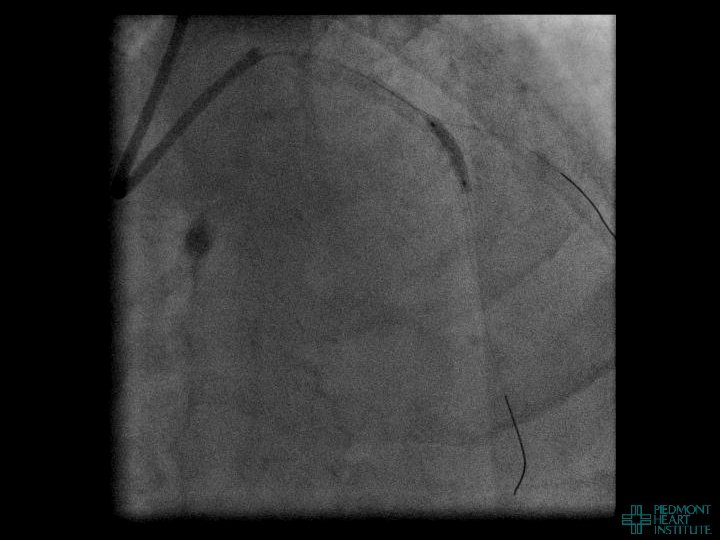

Case Example 3